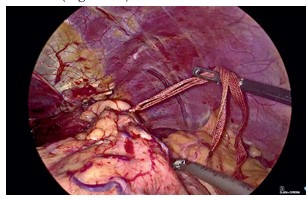

Nissens Fundoplication: A Laparoscopic Edge?

Background: Hiatal hernia often leads to gastroesophageal reflux disease (GERD), which may be refractory to medical therapy. Surgical intervention in the form of Nissens fundoplication can provide definitive relief. With advancements in minimally invasive techniques, the role of laparoscopic Nissens fundoplication is increasingly prominent. Aim: To compare the effectiveness of open versus laparoscopic Nissens fundoplication in patients with endoscopically confirmed hiatal hernia. Objectives: • Compare operative time, symptom relief, and complications in open and laparoscopic procedures. • Evaluate improvement using De-Meester Johnson reflux score. Material: A prospective study involving 38 patients (18-60 years) at a tertiary care hospital over 18 months (Sep 2022 - Mar 2024). Patients were randomized into two equal groups for open or laparoscopic Nissens fundoplication. Results: Both groups showed significant symptomatic improvement. Laparoscopic surgery had a longer operative time (135 vs 110 minutes) but fewer complications and better De-Meester scores Post-operatively. Statistically significant improvement in heartburn, regurgitation, and dysphagia was observed, especially by Postoperative day 7. Conclusion: Laparoscopic Nissens fundoplication is as effective as open surgery in relieving GERD symptoms, with additional benefits of fewer complications and faster recovery, despite longer operative duration.